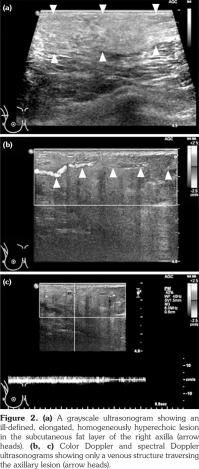

Full-field digital mammography was performed (MAMMOMAT Inspiration; Siemens AG, Munich, Germany). A right mediolateral oblique view revealed an asymmetric density in the right axilla (Figure 1). Ultrasonography was performed with a 5- to 12-MHz linear transducer (iU22; Philips Medical Systems, Bothell, WA, USA), which identified a poorly defined, elongated, homogeneously hyperechoic lesion in the subcutaneous fat layer of the right axilla (Figure 2). The lesion did not exhibit increased vascularity, except for a normal traversing venous structure (Figure 2). The lesion was surgically excised. Pathological examination confirmed the diagnosis as lipogranuloma (Figure 3). On the other hand, complete blood test results were normal.

Besides the breast and axilla, the ultrasonographic features of lipogranuloma have been described in the penis and scrotum, and have included cases with an ill-defined area of increased echogenicity in the subcutaneous tissue of the penile shaft,(11) a poorly defined extratesticular echogenic mass with an elongated appearance on a longitudinal scan,1 and an intratesticular heterogeneously hypoechoic mass.(12)